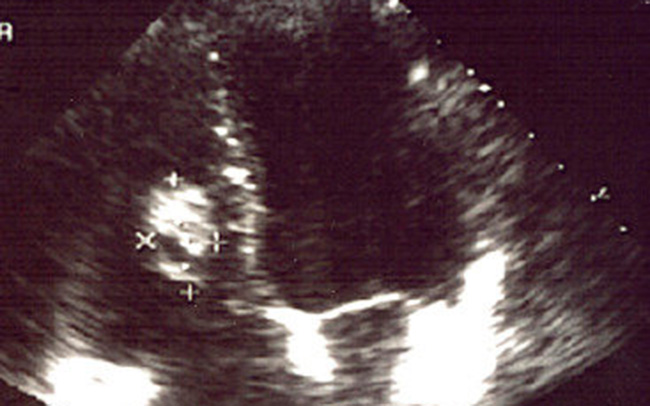

Ultrazvučni pregled srca

Nakon što bude obavio pregled kod kardiologa, pacijent može da bude upućen i na ultrazvučni pregled srca.